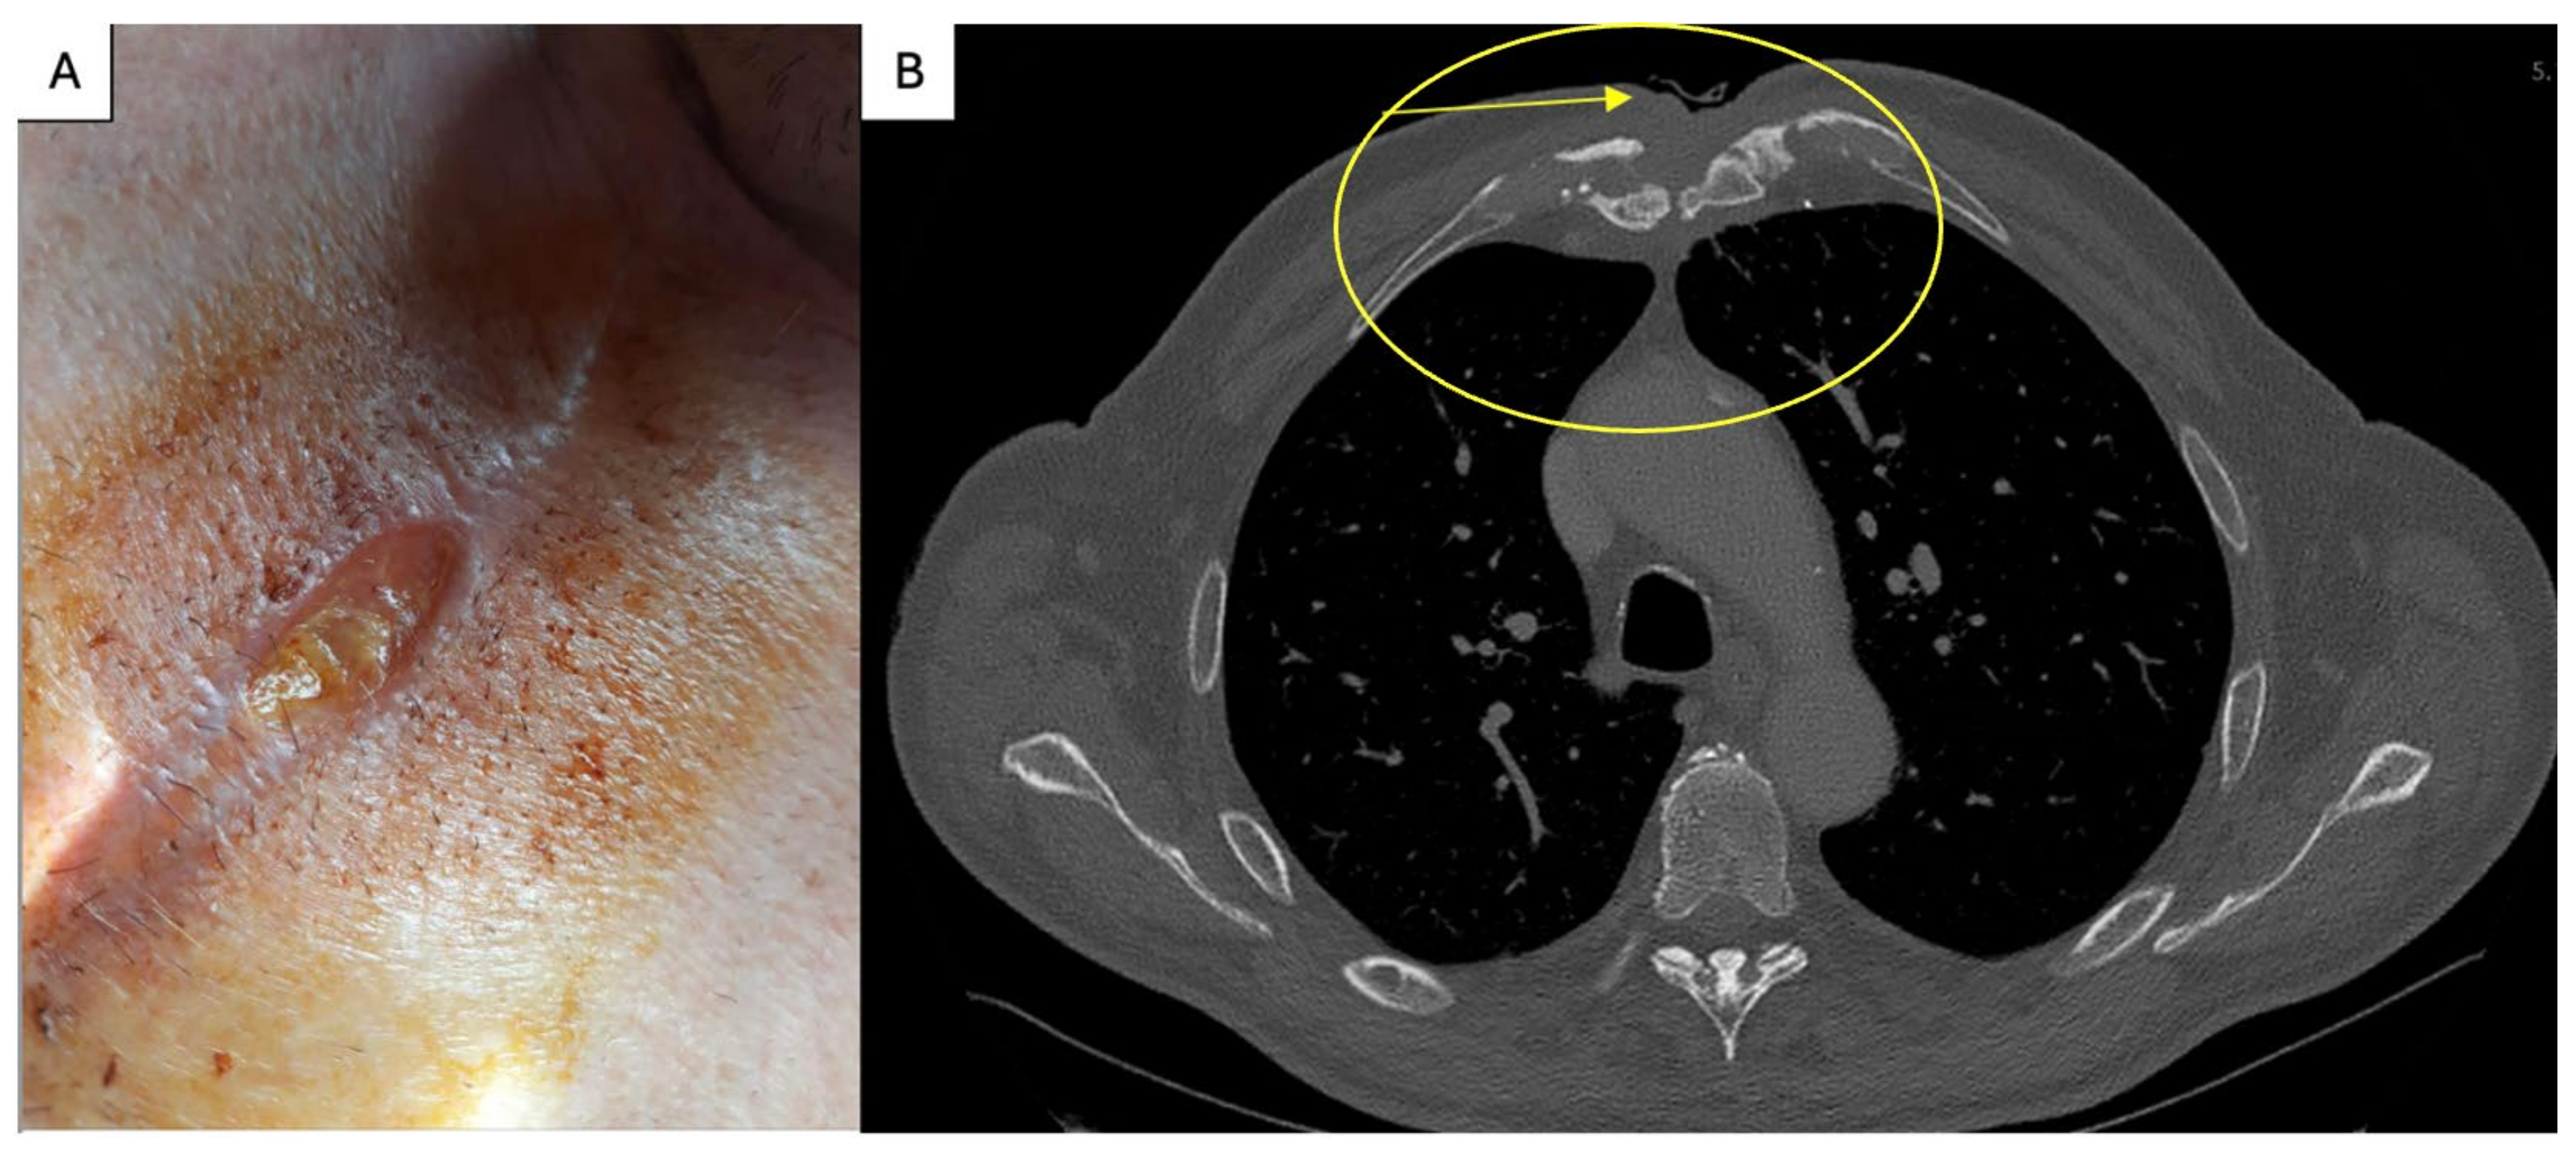

2. Case Report